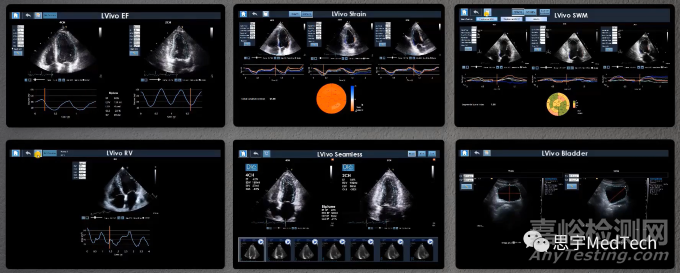

該公司旗下還有諸多類似AI軟件系統(tǒng),統(tǒng)稱為LVivo Toolbox,包含:LVivo Seamless,LVivo EF,LVivo RV,LVivo Strain,LVivo SWM,LVivo Mobile,LVivo SAX,LVivo Bladdar,均已獲得FDA和CE認(rèn)證。

▲公司旗下全線軟件系統(tǒng)